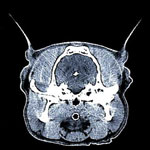

●頭部

まっすぐに歩けない、けいれんがおきる、鼻水が治らない、耳がいつも汚れている、

目が飛び出している、

顔が腫れているetc…